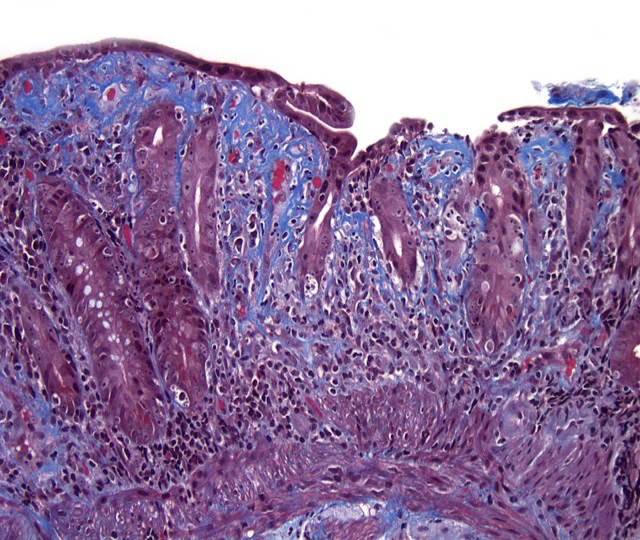

Microscopic (histologic) description

- Histological elementary lesions (Dig Liver Dis 2011;43:S385, Semin Diagn Pathol 2014;31:124):

- Increased intraepithelial T lymphocytes (IEL):

- 25 - 29 IEL/100 enterocytes is considered borderline

- > 30 IEL/100 enterocytes represents a pathological lymphocytosis

- Decreased enterocyte height, flattening of enterocytes, intracytoplasmic vacuolation and reduction or absence of brush border are suggestive but not specific

- Crypt hyperplasia:

- Extension of the regenerative epithelial crypts associated with changes in the presence of more than 1 mitosis per crypt

- Villous atrophy:

- Decrease in villous height, normal villous:crypt ratio (3:1) until total disappearance of villi

- This assessment requires proper orientation of the biopsies

- Increased intraepithelial T lymphocytes (IEL):

- Diagnostic categories are based on these elementary lesions:

- Modified Marsh-Oberhuber classification of histologic findings in celiac disease

- Simplified systems (Corazza & Villanaci or Ensari), which may be more reproducible (Arch Pathol Lab Med 2010;134:826, Pathol Res Pract 2016;212:1174)

- Different grades of duodenal mucosal lesions:

- Grade A / type 1: increased intraepithelial lymphocytes but no villous atrophy

- Grade B1 / type 2: villi still present but shortened

- Grade B2 / type 3: complete villous atrophy

Microscopic (histologic) images

- Collagenous sprue:

- Patchy, excessive, subepithelial collagen deposits